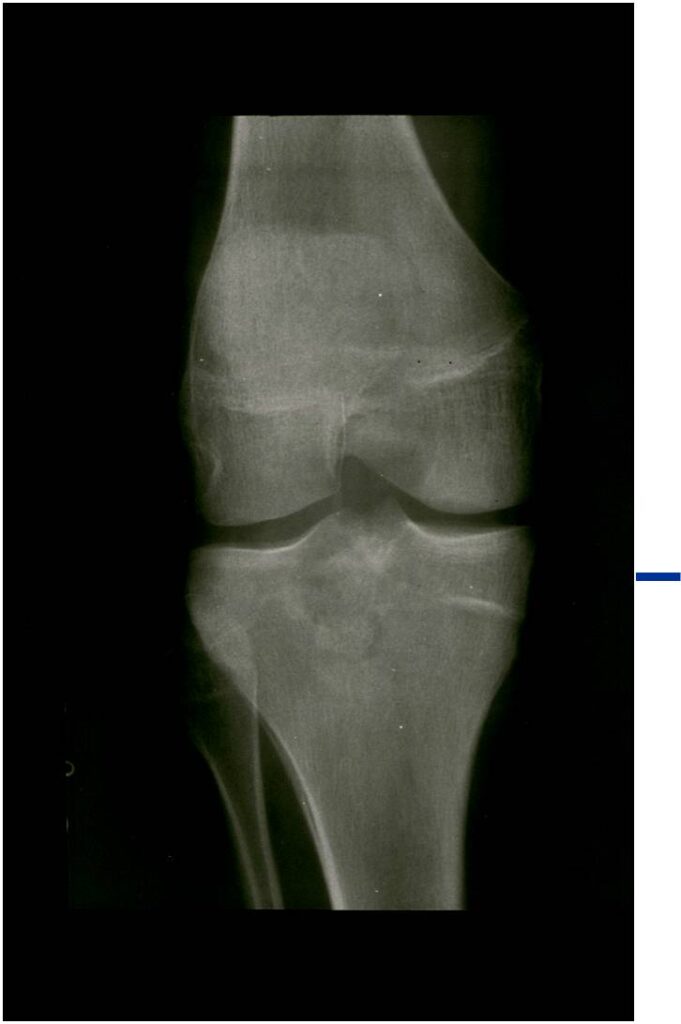

Radiographic Presentation

- Presents as a highly defined/well circumscribed geographic oval/round lytic defect

- Surrounded by rim of sclerotic bone

- Usually in epiphyseal region

- Lesion ranges from 3 cm to 6 cm diameter

- Usually radiolucent

- May have fine trabeculae and irregular calcifications

- Calcifications are often better detected with a CT scan but are not uniformly present

- Lesions may expand the bone and new periosteal bone may form

- Bony end plate, cortex, bone contour are unaffected

- (Plain x-ray appearance)

- Geographic lytic lesion IA/IB margin of sclerosis

- Usually Eccentric more often than Central in the bone

- Rarely expansile (rarely penetrates the cortex)

- Calcified chondroid matrix 30%-50% of cases

- Often better detected with a CT Scan

- Periosteal Reaction 30-50% of cases

- Usually occurs in Adjacent Diaphysis/Metaphysis since epiphysis is intraarticular and not surrounded by periosteum